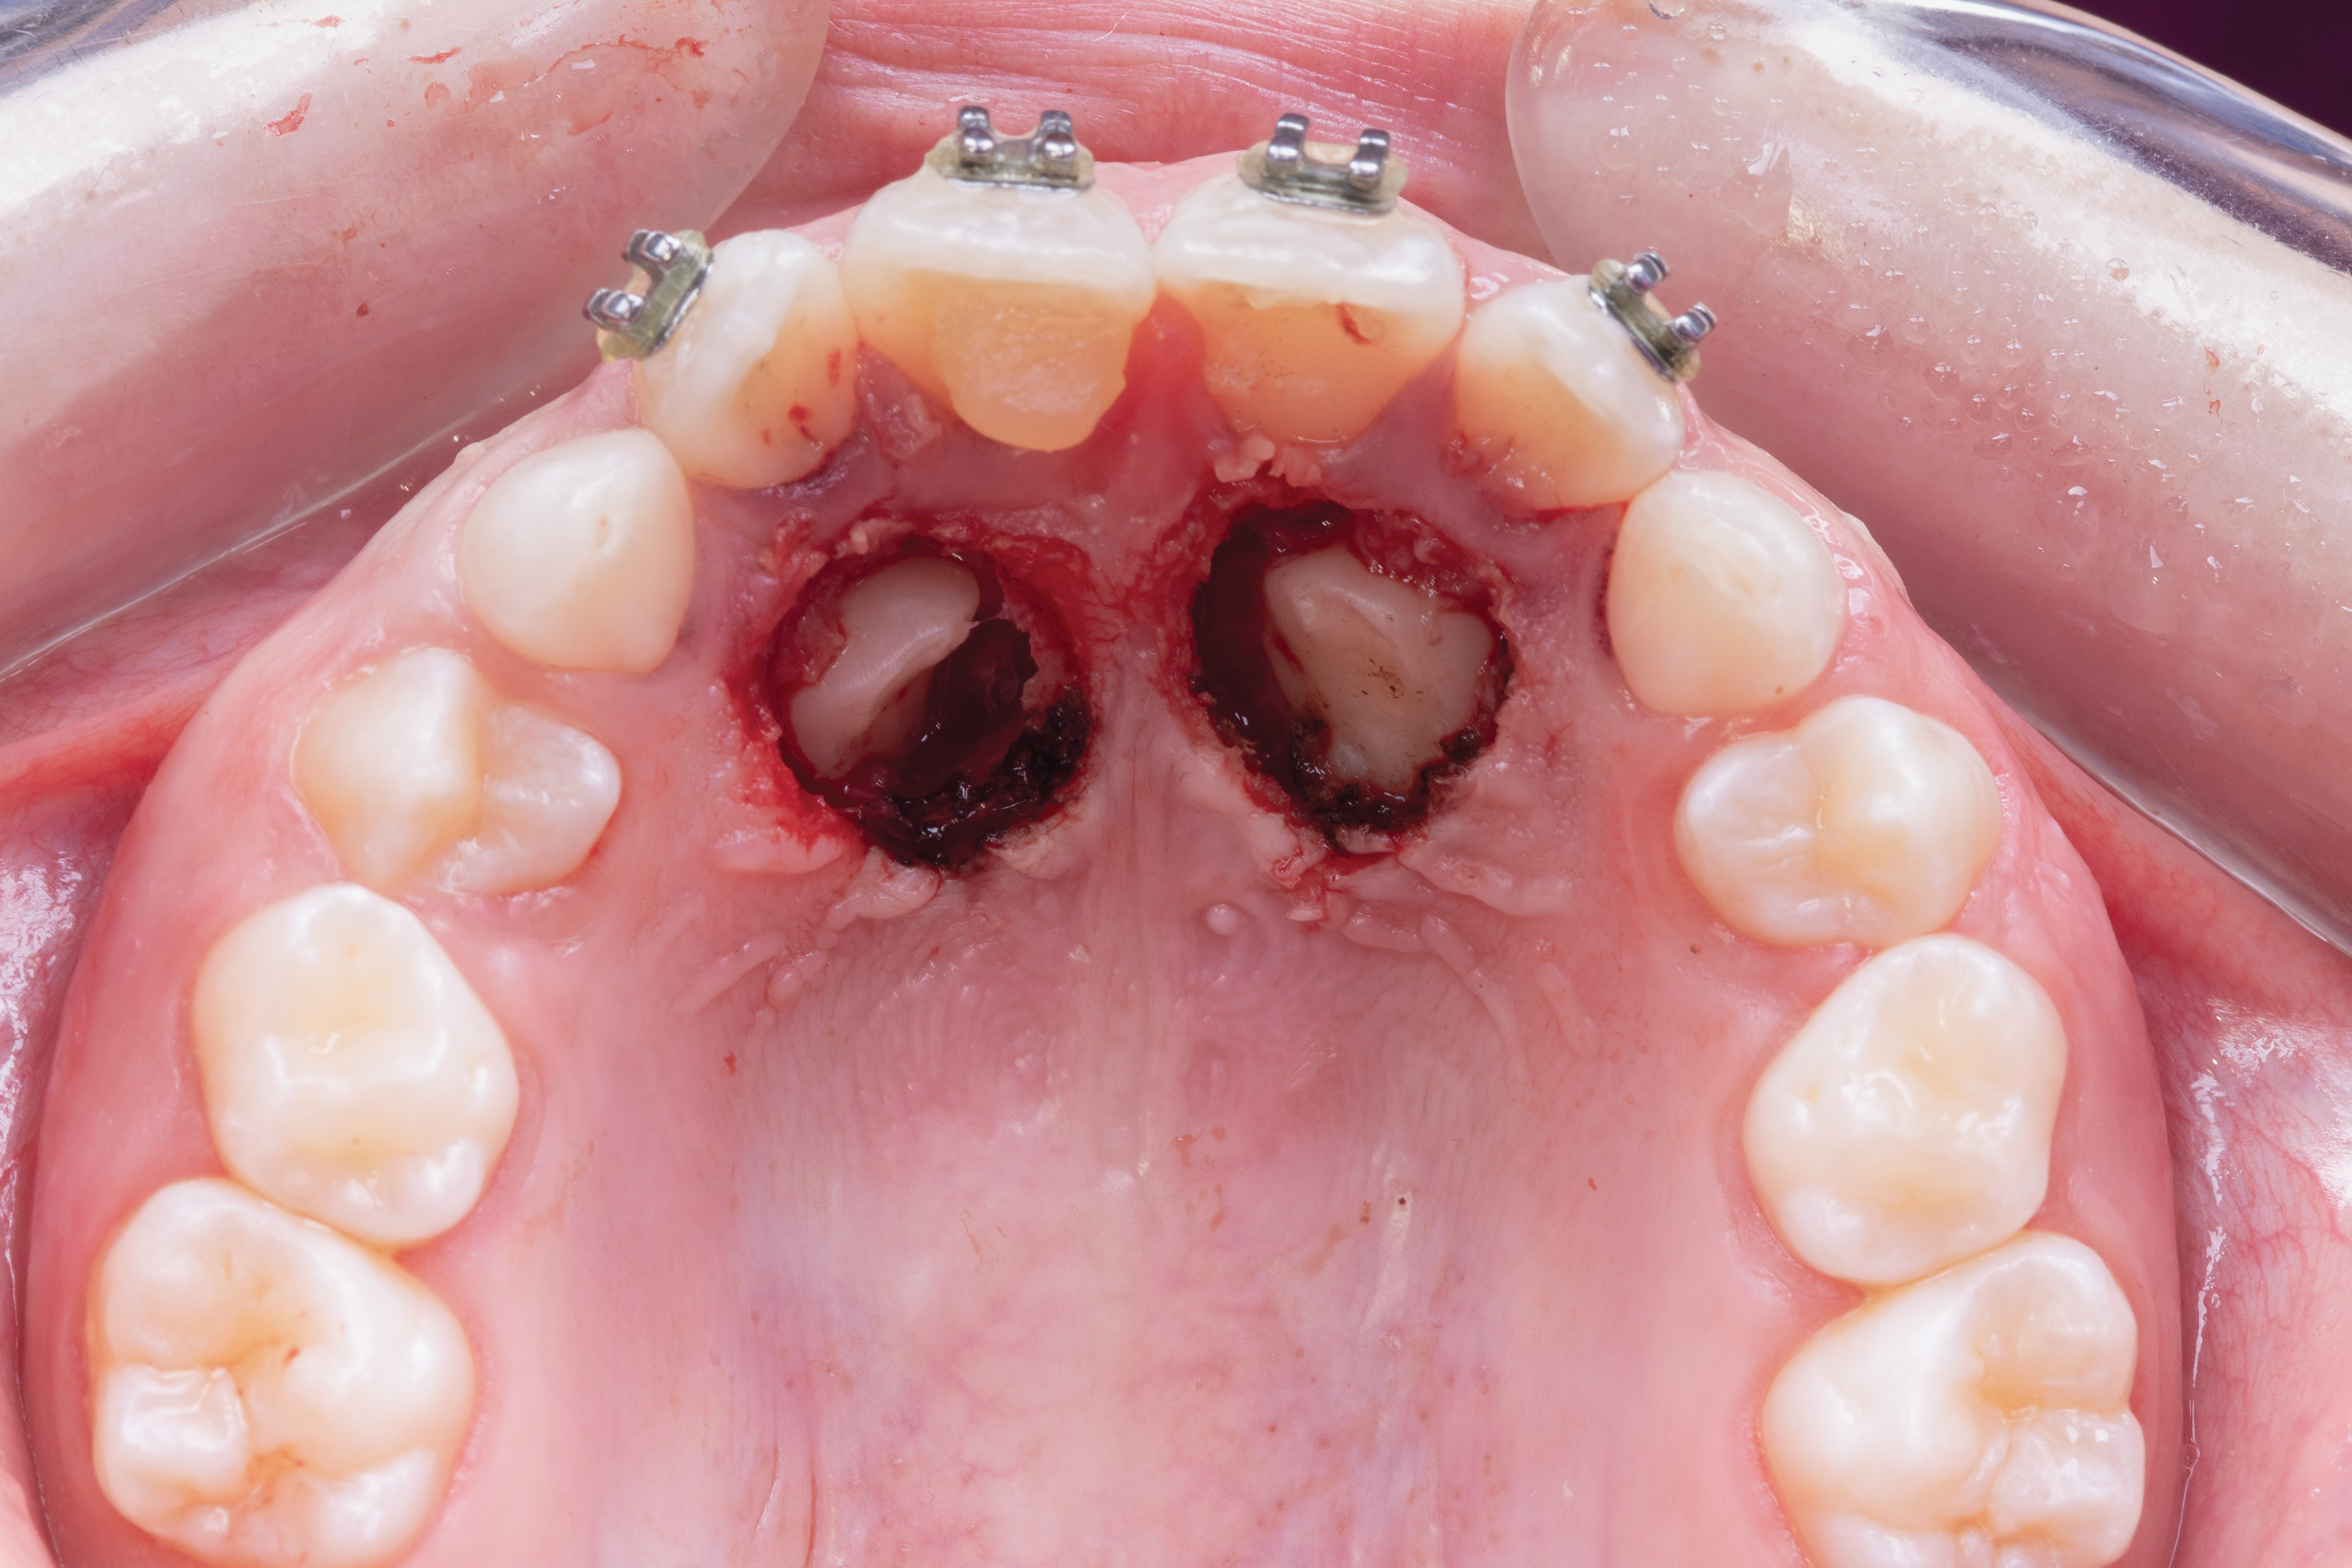

To obtain more information with greater detail, a volumetric study such as a cone-beam computed tomography (CBCT) is often indicated. This advanced imaging technology may be used for the assessment of root resorption in adjacent teeth,24,25 possible transpositioning between the maxillary lateral incisor and canine or in maxillary canines erupting just above the apexes of the lateral incisors,26,27 root dilacerations, and ankylosis.8 Regarding root resorption, Ericson and Kurol reported that, based on tomography, 38% of maxillary lateral incisors and 9% of maxillary central incisors presented important root resorption in relation to impacted canines (Figure 2 and Figure 3).24

Fig 2 scans of palatal impacted canines; front view (Fig 2) and occlusal view (Fig 3).

Figure 2

Fig 3. CBCT scans of palatal impacted canines; front view (Fig 2) and occlusal view (Fig 3).

Figure 3